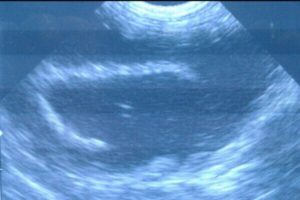

Они привезли своего питомца в «Донской ветеринарный госпиталь». Врач внимательно осмотрел животное и даже сделал УЗИ. Снимок показал, что в кишечнике хищницы есть посторонний предмет. Специалистам ничего не оставалось, кроме как подготовиться к операции.